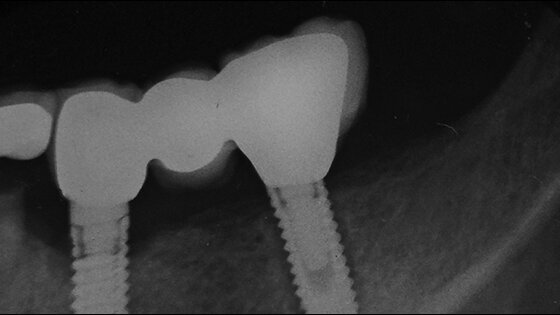

– 6. 4. 2014 zavedení implantátu 3,2 × 13 mm Implant Direct (obr. 6);

– 21. 6. 2014 nahrazení zubů dvoučlennou metalokeramickou rekonstrukcí cementovanou pomo-cí Temp Bondu (obr. 7); udržovací kontrola jeden rok post operationem 10. 8. 2015 prokázala zdravý funkční výsledek (obr. 8).

1. Byl změřen axiální řez na CBCT, na kterém úhel požadovaný pro bezpečnou inzerci implantátu (35 °) je korespondující s nejdelší potřebnou délkou implantátu (13 mm) a průměrem (3,2 mm) (obr. 9).